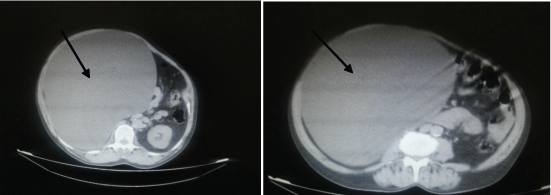

We report here a 65-year-old man who presented in the General Surgery outpatient department of the hospital with pain abdomen since 2 weeks and abdominal distension since one year. He was examined as per standard clinical protocols. On general examination he was moderately built and moderately nourished with a huge firm abdominal mass in the right hypochondrium extending into the epigastrium, right lumbar region and extending down to a point 5cm above the anterior superior iliac spine. The other systemic examinations were normal. Ultrasound (USG) examination of the abdomen revealed a cystic lesion in right hypochondrium extending into the epigastrium causing displacement of liver and the right kidney laterally for which a clinical diagnosis of Hydatid cyst or cystic hemangioma was made. Computerized tomography (CT) scan of abdomen revealed a large 25 x 23 cm cystic mass filling the right hypochondrium, epigastric, right flank upto the right iliac fossa and a radiological diagnosis of mesenteric cyst or retroperitoneal cyst of undetermined origin was offered [Table/Fig-1]. The patient was investigated for his Liver function and full blood count, which were within normal limits. The patient underwent a laparotomy that revealed a large cyst attached to the inferior surface of liver which was followed by a cystectomy and the fully resected cyst was sent for histopathological examination.

Abdominal CT showing an unilocular cystic mass filling the right hypochondrium, epigastric region causing displacement of right kidney.